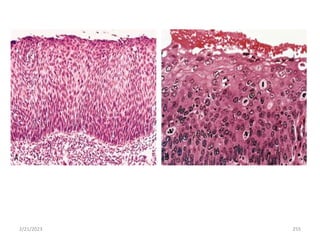

Figure Metaplasia of columnar to squamous epithelium. A, Schematic

diagram.

B, Metaplasia of columnar epithelium (left) to squamous epithelium

(right) in a bronchus.